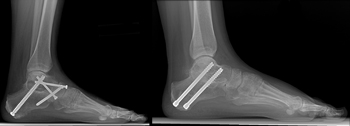

The patient shown in these x-rays had arthritis of the hindfoot. It was treated by fusing all three joints of the hindfoot (triple fusion). An ankle replacement was also done in order to improve mobility and avoid the severe stiffness that would result from another ankle fusion. The ankle replacement implants can be seen here from the front and the side.

These x-rays show an ankle fusion from the front and the side. The number and placement of screws and the use of a plate are dependent upon the surgeon's technique.